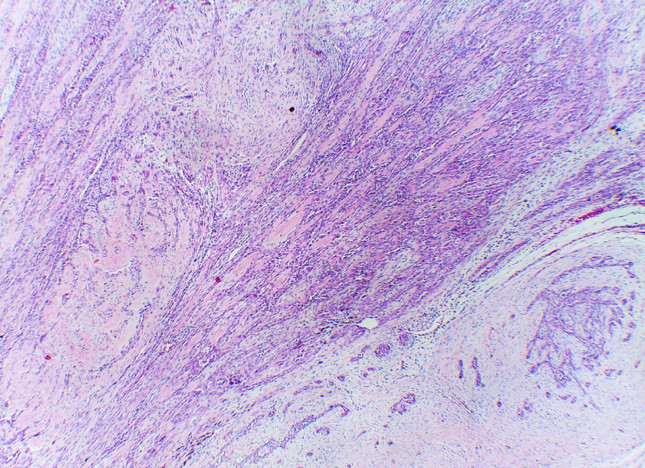

Tumor de células fusiformes con diferenciación semejante a timo (SETTLE por sus siglas en inglés).